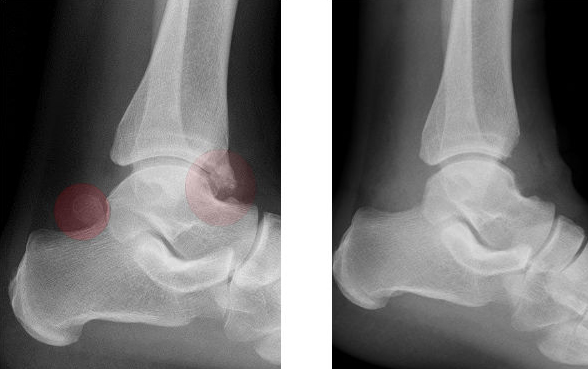

Röntgenbild eines Sprunggelenkes vor und nach Entfernung eines os trigonum und eines knöchernen Sporns (Osteophyt) - beides rot eingekreist